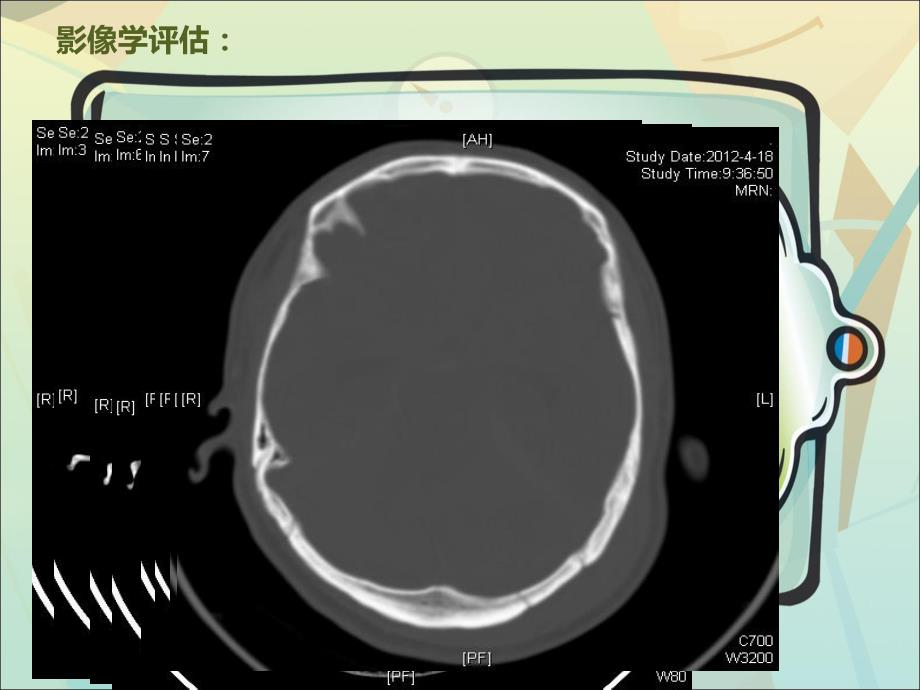

1、 病例讨论病例讨论颅内压监测颅内压监测在重型颅脑损伤治疗中的在重型颅脑损伤治疗中的应用体会应用体会病史情况病史情况:患者某某,男性,43岁,因“头部外伤后昏迷3小时”入院。伤后即刻出现意识障碍。来院时呈昏迷状,潮式呼吸,口唇发绀,很快出现自主呼吸停止,急诊抢救室予气管插管,呼吸机辅助呼吸。T 38.0,P 143次/分,BP223/105mmHg,深昏迷,GCS3-4,双侧瞳孔等大等圆,约2.5mm,直接、间接对光反射消失。眼球固定,左侧外耳道有活动性溢血。颈抵抗,四肢无自主活动,双侧巴氏征阳性。影像学评估:诊断诊断:1.特重型闭合性颅脑损伤 1.1左枕、桥脑小脑角硬膜下血肿(冲击部位)1.2